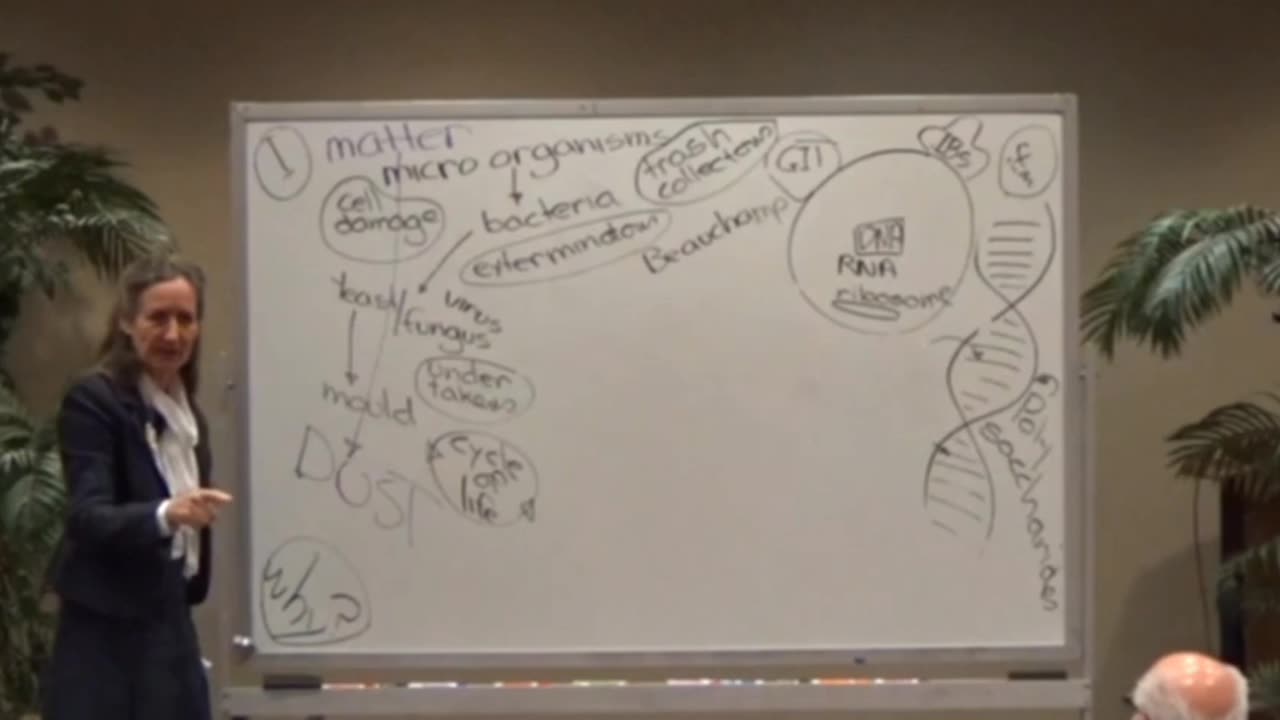

Microbiome & the Gut Brain

BARBARA O’NEILL WHAT ARE BONES MADE OF?

Barbara ONeill -Recipe for Flu Bomb